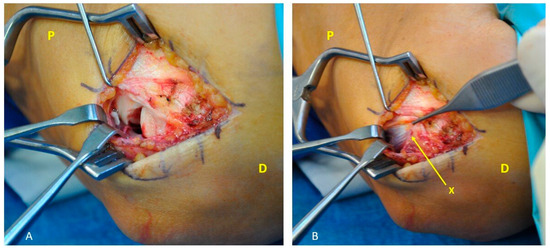

A Novel Modification of Anconeus Muscle Flap for Extensor Digitorum Communis-Selective Lateral Epicondylitis: Preliminary Clinical Study

Surgeries 2025, 6(4), 105; https://doi.org/10.3390/surgeries6040105 - 25 Nov 2025

Introduction: Lateral epicondylitis (LE) typically affects the extensor carpi radialis brevis (ECRB) tendon, while isolated degeneration of the extensor digitorum communis (EDC) origin is rare and poorly characterized. Surgical debridement of these lesions may result in capsular exposure requiring soft-tissue coverage, which can be achieved through a vascularized muscle flap to enhance tendon healing potential and reduce recurrence. This study aimed to describe a modification of the anconeus rotation flap as originally described by Almquist in 1998, and to evaluate its clinical and functional outcomes in patients with isolated EDC tendinopathy. The modified technique consists of a simpler muscle advancement (AMA) that preserves the distal vascular pedicle and reduces soft-tissue dissection. Methods: A retrospective study was conducted on 12 consecutive patients with lateral epicondylitis with isolated EDC tendon involvement (10.71% of all operative cases at our Institution between 2019 and 2022), who were surgically treated with the anconeus muscle advancement modification. Clinical outcomes, including the visual analog pain scale (VAS), grip strength and patient-reported outcome measures (PROMs), which include the QuickDASH score, the Mayo Elbow Performance Score (MEPS) and the Patient-Rated Tennis Elbow Evaluation (PRTEE) score were assessed. Paired statistical tests with 95% confidence intervals and minimal clinically important difference (MCID) thresholds were applied. Results: At a mean follow-up of 38 months, all outcomes demonstrated statistically significant and clinically meaningful improvements (p < 0.05). Reductions in pain/disability (VAS, QuickDASH, PRTEE scores) and functional gains (Grip strength, MEPS) far exceeded their respective MCID thresholds, with 100% attainment for each outcome. Conclusions: This modified anconeus muscle advancement appears to be a technically feasible option for managing isolated EDC-related lateral epicondylitis, preserving vascular integrity while limiting dissection. Although favorable results were obtained, the small retrospective cohort precludes definitive conclusions regarding efficacy. The findings support the technical feasibility of the proposed modification and warrant further prospective comparative investigations.